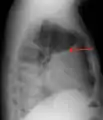

Imaging

A pleural effusion appears as an area of whiteness on a standard posteroanterior chest X-ray.[12] Normally, the space between the visceral pleura and the parietal pleura cannot be seen. A pleural effusion infiltrates the space between these layers. Because the pleural effusion has a density similar to water, it can be seen on radiographs. Since the effusion has greater density than the rest of the lung, it gravitates towards the lower portions of the pleural cavity. The pleural effusion behaves according to basic fluid dynamics, conforming to the shape of pleural space, which is determined by the lung and chest wall. If the pleural space contains both air and fluid, then an air-fluid level that is horizontal will be present, instead of conforming to the lung space.[13] Chest radiographs in the lateral decubitus position (with the patient lying on the side of the pleural effusion) are more sensitive and can detect as little as 50 mL of fluid. Between 250 and 600mL of fluid must be present before upright chest X-rays can detect a pleural effusion (e.g., blunted costophrenic angles).[14]

Chest computed tomography is more accurate for diagnosis and may be obtained to better characterize the presence, size, and characteristics of a pleural effusion. Lung ultrasound, nearly as accurate as CT and more accurate than chest X-ray, is increasingly being used at the point of care to diagnose pleural effusions, with the advantage that it is a safe, dynamic, and repeatable imaging modality.[15] To increase diagnostic accuracy of detection of pleural effusion sonographically, markers such as boomerang and VIP signs can be utilized.[16]